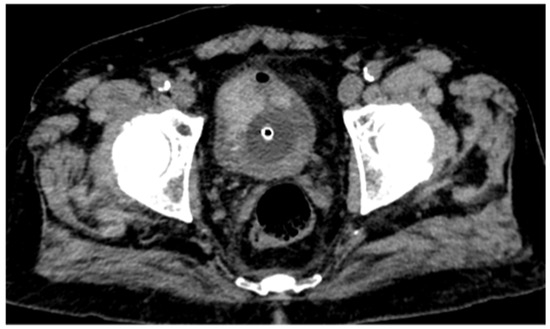

CT urography, through its multiphase protocol, enables the identification of key radiological findings that contribute to diagnostic assessment. In the conventional unenhanced phase, two hyperdense areas are observed: one along the left posterolateral bladder wall, and another protruding into the lumen at the level of the anterior wall and bladder dome (Figure 1).

Figure 1. Conventional unenhanced CT scan shows a large hyperdense lesion on the anterior bladder wall and a mildly hyperdense area along the left posterolateral wall. Further evaluation with intravenous contrast medium administration is required to better characterize these findings.